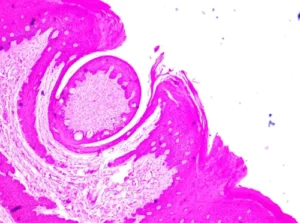

نبني تجربة تعلمك حول التفاعل والتطبيق. من خلال مقاطع فيديو عالية الجودة، والصور التوضيحية التفاعلية، والاختبارات التكيفية التي تركز على الفهم وليس التلقين، نحول الدراسة إلى رحلة استكشافية نشطة.

نعرض لك كيف يتكامل علم التشريح مع علم وظائف الأعضاء، وكيف تؤثر الكيمياء الحيوية على علم الأدوية، لترى الصورة الكاملة لجسم الإنسان